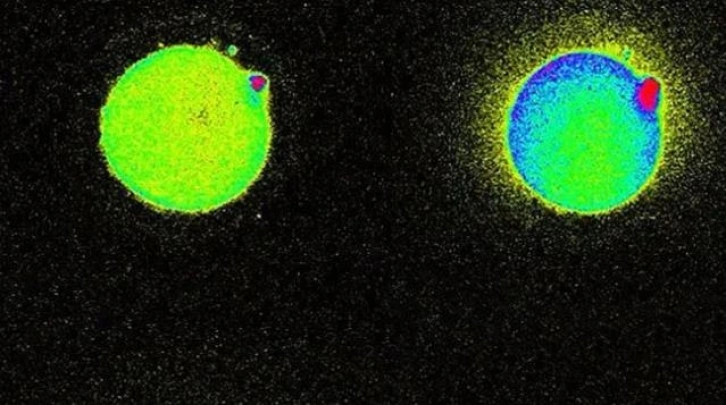

Mucizevi olay daha önce hayvanlarda gözlemlenmişti. Ancak bugüne kadar insanlardaki bu parıltıyı gözlemleyebilen olmamıştı. Bir şaşırtıcı şey ise bazı yumurtalar diğerlerinden daha fazla parlak parlıyor, bu da sağlıklı bir embriyo oluşturabilme konusundaki yeteneklerini gösteriyor.

Bu olayı nasıl kanıtlayacaklarını yıllarca düşünen bilim insanları 2014 yılında bu olayı ilk defa gözlemlemiş, ve sperm yumurtayı deldiği anda salgılanan serbest duruma geçen milyarlarca çinko atomunu seyretmişti.

Yeni bir flörasan algılayıcı kullanarak canlı hücrelerdeki çinko atomu hareketlerini takip eden bilim ekibi, yumurtadaki çinko depolama yeteneğini fark etti. Yaklaşık 8000 değişik küçük haznede depolanan 1 milyon civarında çinko atomu döllenme gerçekleşince havai fişek gibi ateşleniyor. Döllenmenin ardından 2 saat boyunca bu olay devam ediyor. Kaynak: Süperileri.com, Nature.com